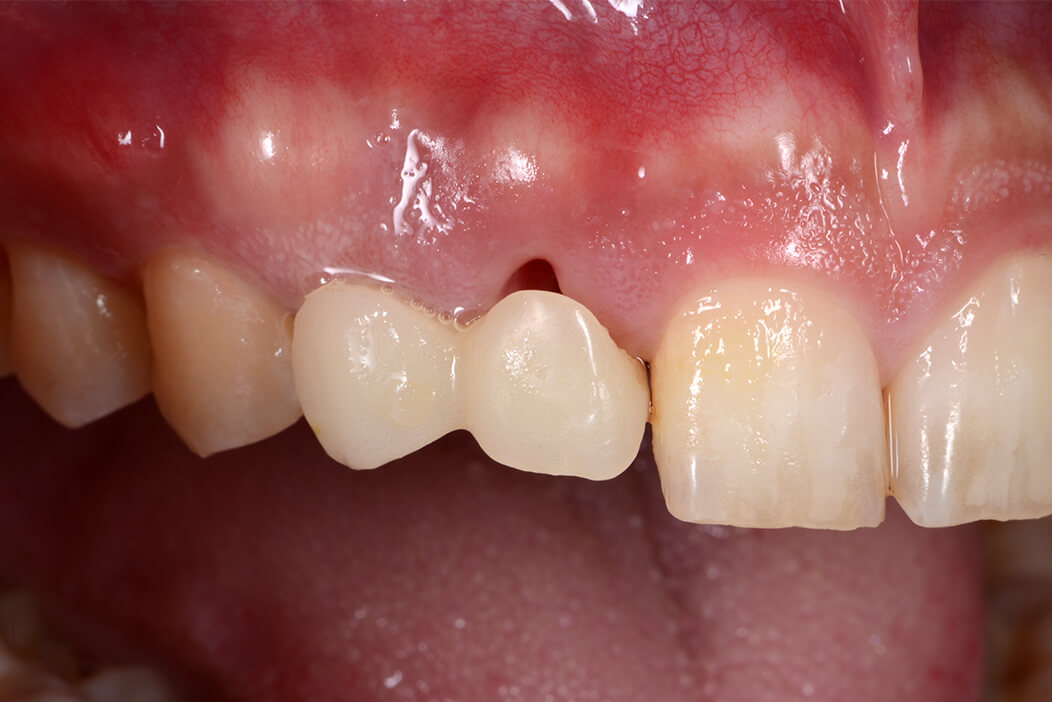

症例3 上顎右側前歯部に抜歯即時インプラント治療を行なった症例

上顎右側前歯部に抜歯即時インプラント治療を行なった症例

男性/30代

費用/737,000円

治療期間/4ヶ月

治療内容の詳細/

保存不可能な上顎右側前歯部(乳歯の晩期残存と残根歯)のインプラント治療を希望。

2本の保存不可能な歯を抜歯し、即日にインプラントを埋入する抜歯即時インプラント治療を適用。術前にX線、CT撮影、インプラント治療のシミュレーションを行い、スペースが少ないため2本の欠損に対して1本のインプラントを計画。コンピューターガイデッドサージェリーを用いてストローマン社製BLXインプラントをフラップレスにて適切な位置に埋入し、即日に仮歯も装着して見栄えも考慮し、低侵襲な治療ができました。3ヶ月後口腔内スキャナーでデジタル印象を行い、スクリュー固定式のジルコニアセラミッククラウンを作成し装着しました。